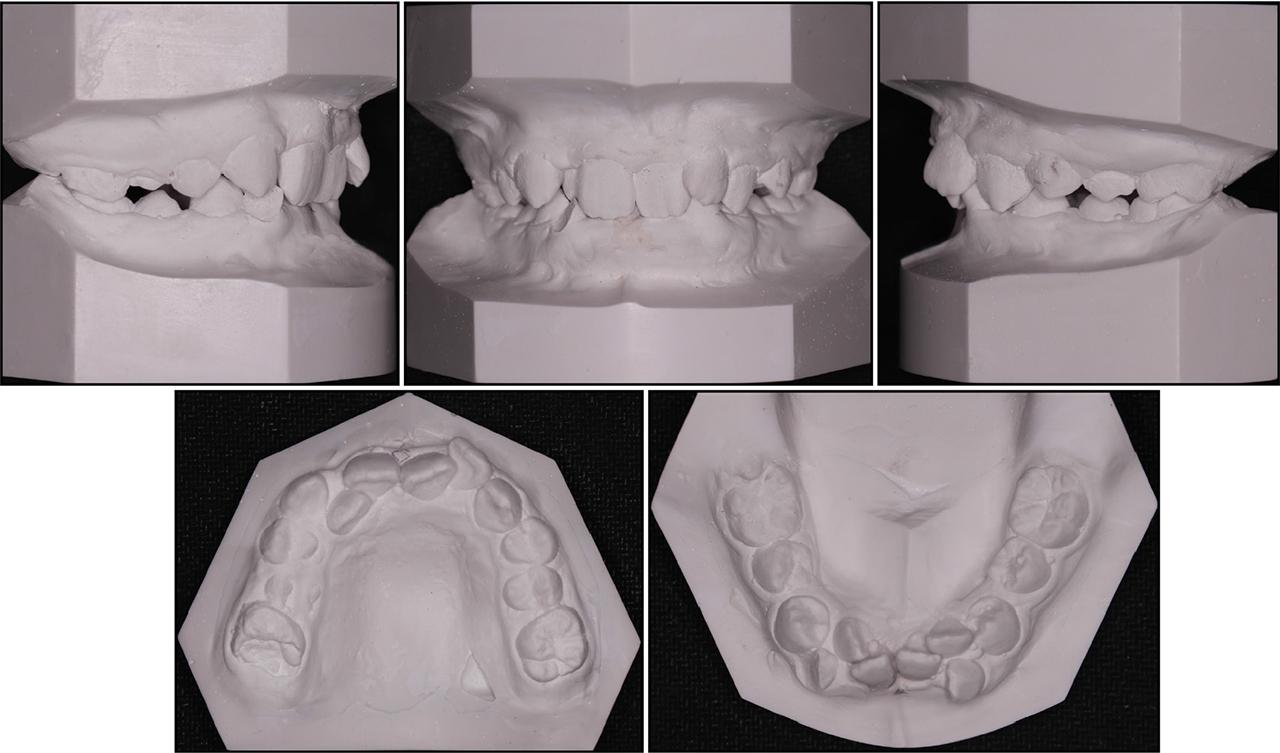

Figure 1